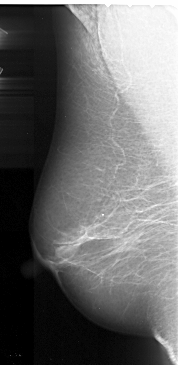

A_1048_1.LEFT_MLO

LEFT_MLO LINES 5101 PIXELS_PER_LINE 2491 BITS_PER_PIXEL 16 RESOLUTION 42 NON_OVERLAY